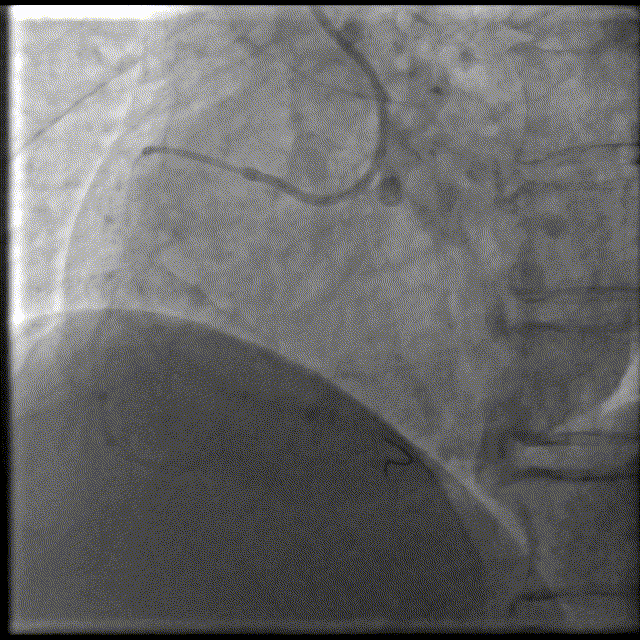

PCI术后结果及随访

• 即刻结果:支架成功植入

• 远期结果:随访,强化抗血小板

• 后期的处理?可能存在的风险?:支架血栓风险,近中段内膜有否损伤